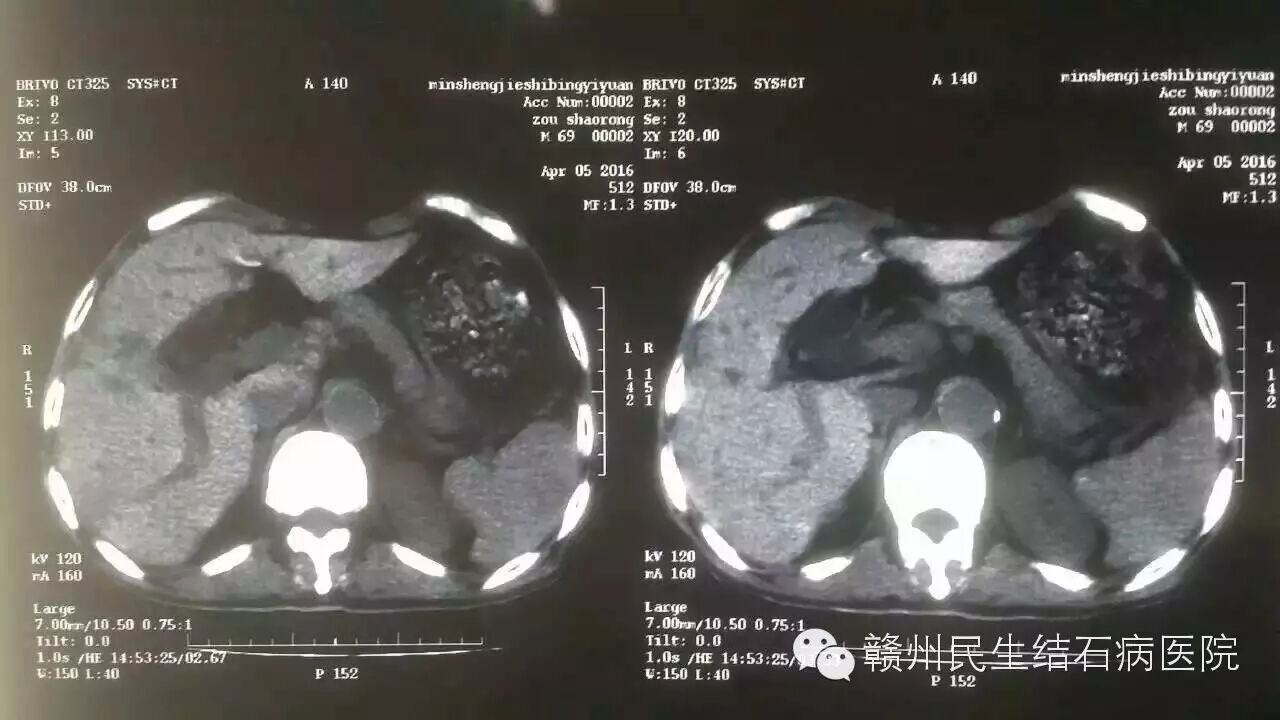

术前CT检查